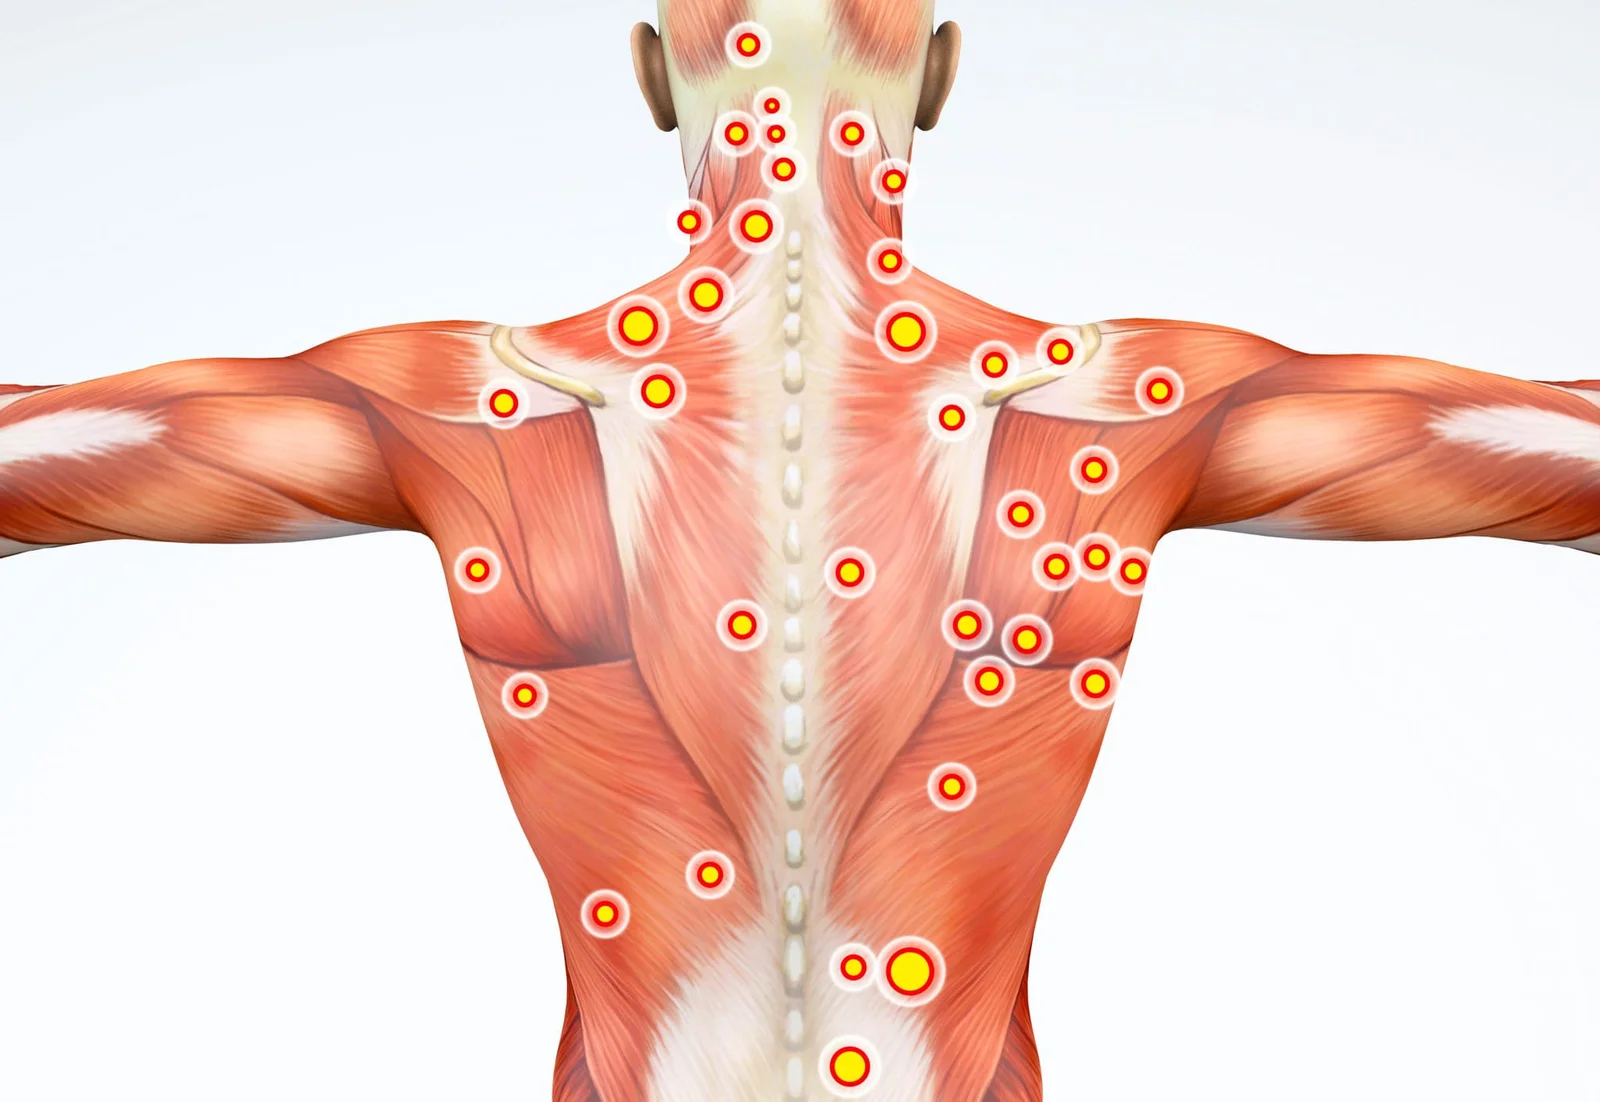

La deuxième branche de la podologie concerne la biomécanique: de manière pratique, elle traite les troubles de la marche, de la course, les problèmes posturaux, l’analyse des muscles et des ligaments en relation avec le pied, les pieds plats/ creux, etc. Celle-ci permet de mettre en relation différentes pathologies du pied avec des segments sous-jacents du corps (genoux, hanches, colonne vertébrale).

Lors de la consultation, le podologue effectue une anamnèse complète, un examen palpatoire des muscles et des ligaments, une analyse de la posture et de la marche. De plus, le podologue définit un traitement sur-mesure et réalise des semelles podologiques adaptées à la pathologie.

- Examen biomécanique